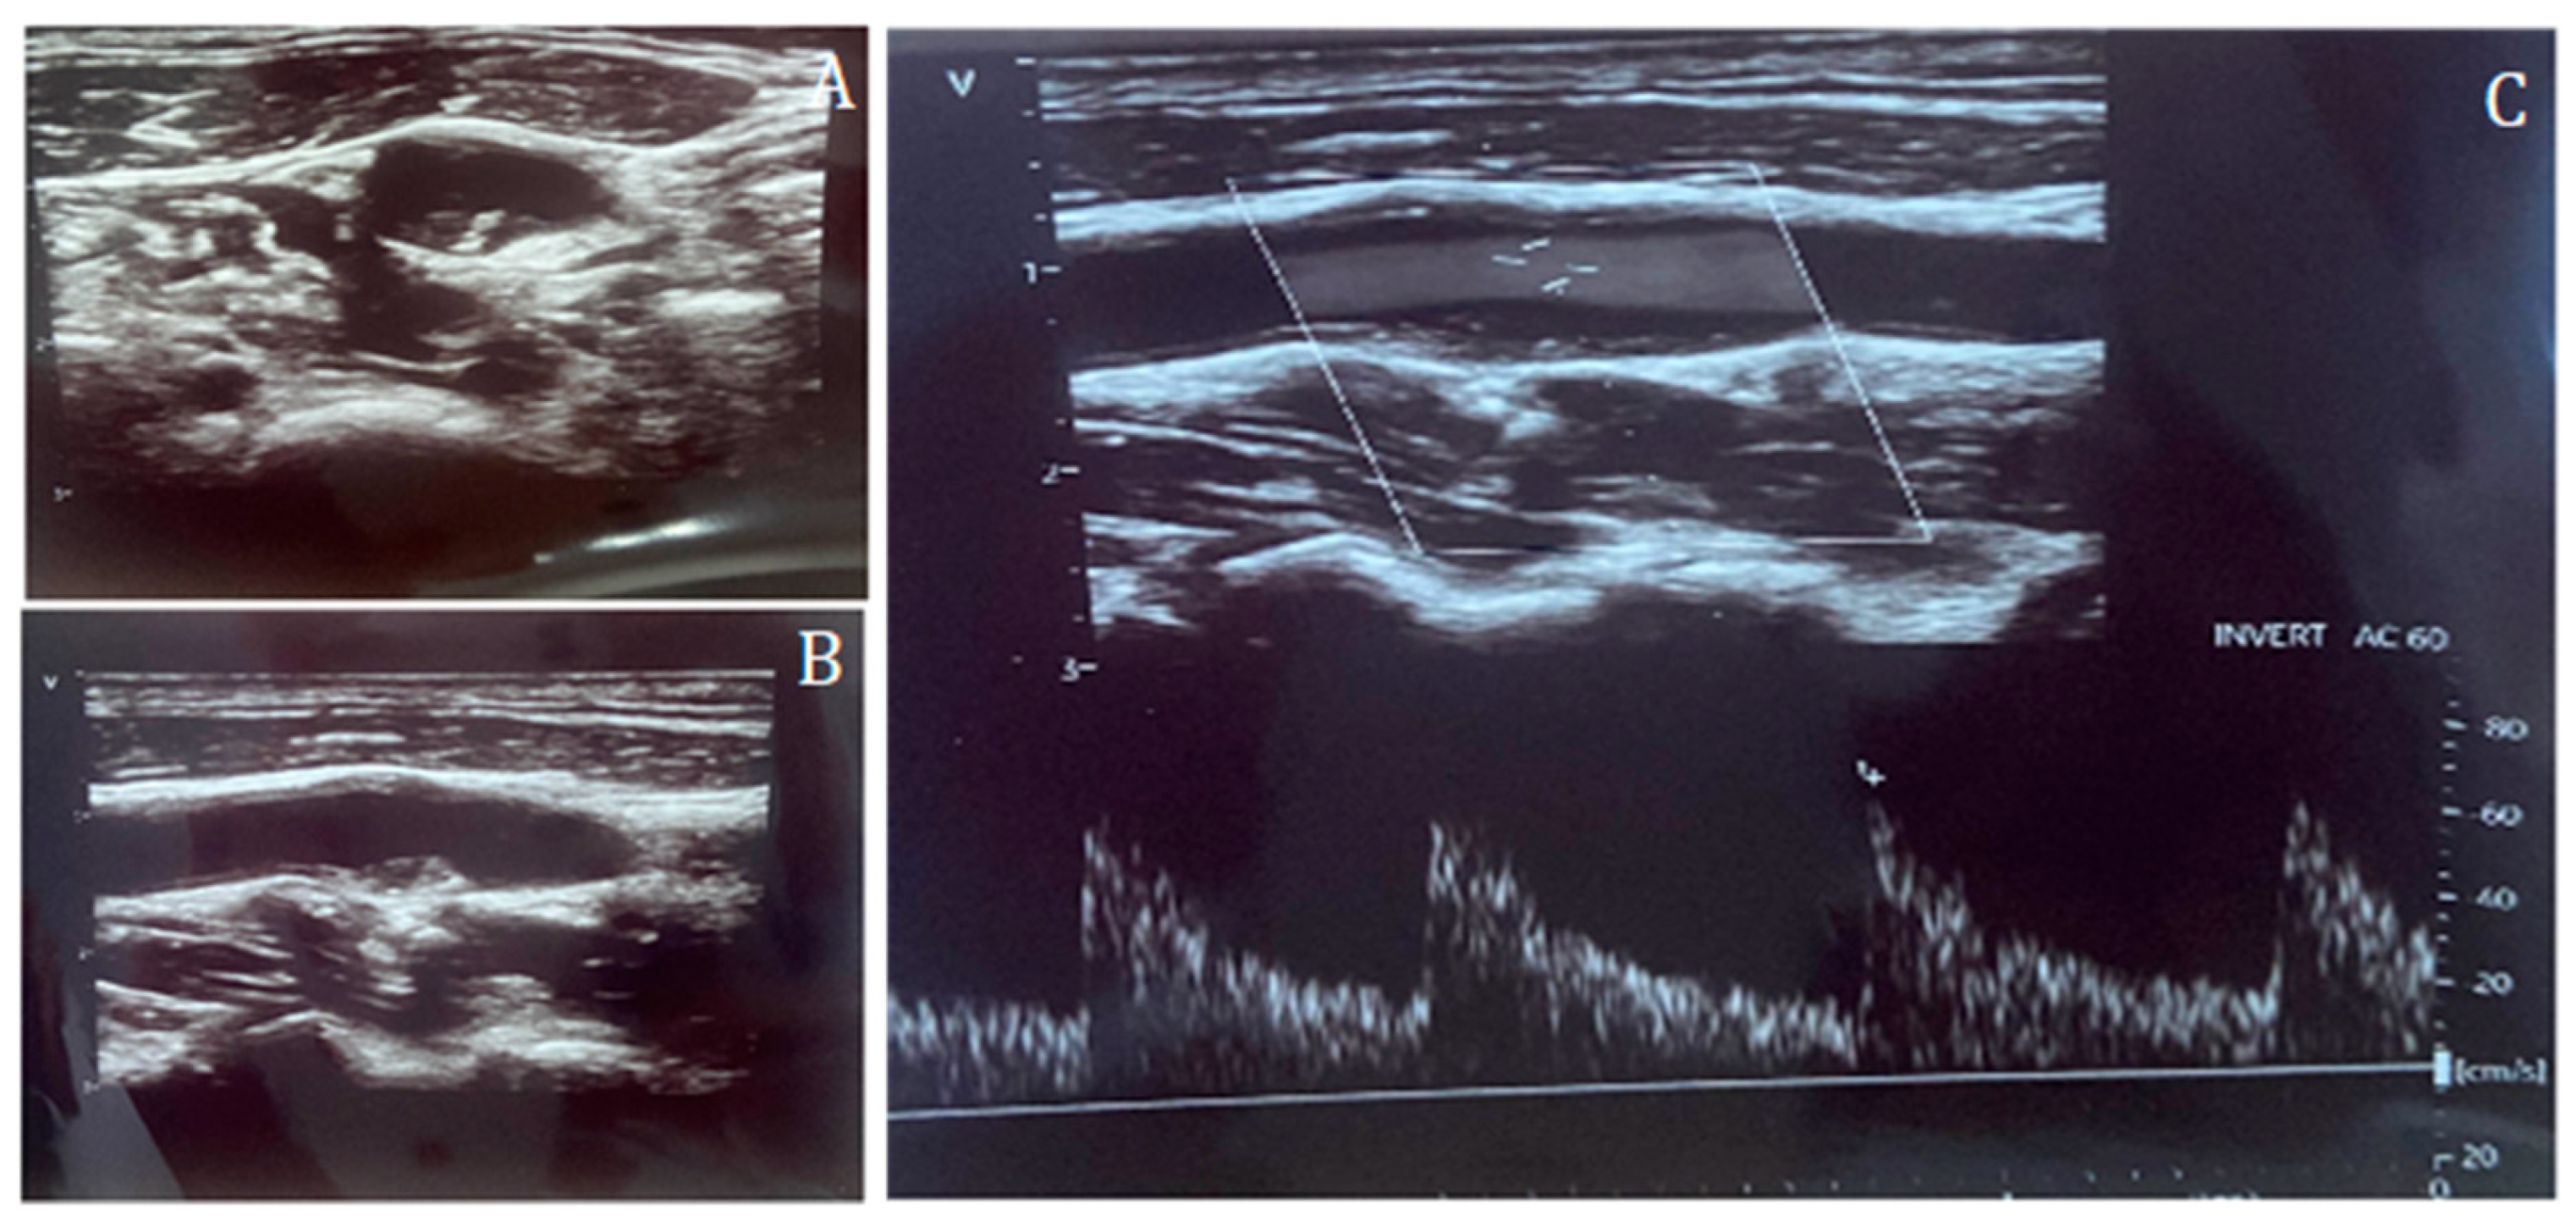

Figure 1.

Carotid duplex ultrasound representation of a non-significant lesion of the internal carotid artery in short-axis (A) and long-axis (B), and Doppler assessment (C), confirming the absence of flow acceleration across the plaque.